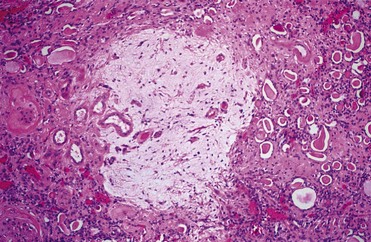

Urinary tract obstruction leads to progressive and, eventually, permanent changes in the structure of the kidney, including the development of tubulointerstitial fibrosis, tubular atrophy and apoptosis, and interstitial inflammation. A number of cytokines and growth factors have been shown to play roles in these events, among which the most prominent include transforming growth factor beta TGF-β, angiotensin II, NFκB, and TNF-α. Some are produced directly from the renal tubular and interstitial cells; others are generated from infiltrating macrophages.

Tubulointerstitial fibrosis develops as a consequence of extracellular matrix being synthesized and deposited at a greater rate than it is degraded, as well as to a relative increase in matrix due to collapse of parenchymal volume as nephrons are destroyed (Hewitson, 2009). A family of enzymes known as matrix metalloproteinases (MMPs), which includes collagenase, normally cleaves and degrades the collagenous and noncollagenous components of the extracellular matrix. Obstruction increases the synthesis of tissue inhibitors of metalloproteinases (TIMPs) that reduce MMP activity, resulting in the accumulation of extracellular matrix. Infiltrating macrophages stimulate TGF-β synthesis, and this growth factor increases TIMP production, thus reducing collagen turnover. Macrophages also produce other cytokines and growth factors, such as interleukin 2, interleukin 6, fibroblast growth factor, and platelet-derived growth factor (PDGF), that appear to contribute to this inflammatory and fibrotic process. Active TGF-β binds directly to its type 2 receptor, which subsequently activates and phosphorylates the type 1 TGF-β receptor. Both of these receptors have been shown to be upregulated in rats with UUO, in both the obstructed and contralateral renal units. This may be a factor in the hypertrophic response sometimes seen in the nonobstructed kidney (Sutaria et al, 1998). The activated type 1 TGF-β receptor subsequently phosphorylates SMAD (mobile transcription factors with a name derived from related genes in Caenorhabditis elegans [Sma] and Drosophila [Mad]) proteins. A heteromeric complex of SMAD proteins translocates to the nucleus, where it interacts with transcription factors to regulate gene transcription (Wamsley-Davis et al, 2004) and stimulates tubulointerstitial fibrosis (Fukasawa et al, 2004). Stimulation of TGF-β furthermore stimulates the JNK1 (c-JUN N-terminal protein kinase 1) pathway, which targets the activation of c-Jun and activates transcription factor 2, which are critical components in activating fibronectin production. Increased mRNA expression of TGF-β is seen as early as 10 hours after obstruction and increases for 4 days (Walton et al, 1992; Diamond et al, 1994). The increase occurs primarily in medullary tubules and the interstitium and is less prominent in cortical tubules or glomeruli. Furthermore, TGF-β interacts with other profibrotic growth factors such as EGF and angiotensin II (Kaneto et al, 1993; Ishidoya et al, 1995; Chevalier et al, 1998).

In summary, obstruction of normal urine outflow results in biochemical, immunologic, hemodynamic, and functional changes. It stimulates a cascade in which elevated levels of angiotensin II, cytokines, and growth factors lead to tubular cell apoptosis and cellular inflammation, increased net matrix formation, and tubulointerstitial fibrosis. Many of the mediators are intrinsic to the renal tubular cells, whereas others are contributed by fibroblasts and by migrating macrophages (Fig. 40–3).

Figure 40–3 Summary of major pathways leading to tubulointerstitial fibrosis and tubular apoptosis as a consequence of ureteral obstruction. Membrane proteins and regulators are discussed in the text. ang II, angiotensin II; HGF, human growth factor; HSPs, heat shock proteins; IGF, insulin-like growth factor; JAK/STAT, Janus kinase/signal transducers and activators of transcription; mφ, macrophages; MAP, mitogen-activated protein; NF-κB, nuclear factor κB; TGF, transforming growth factor; TNF, tumor necrosis factor; TNFR1, tumor necrosis factor receptor 1.